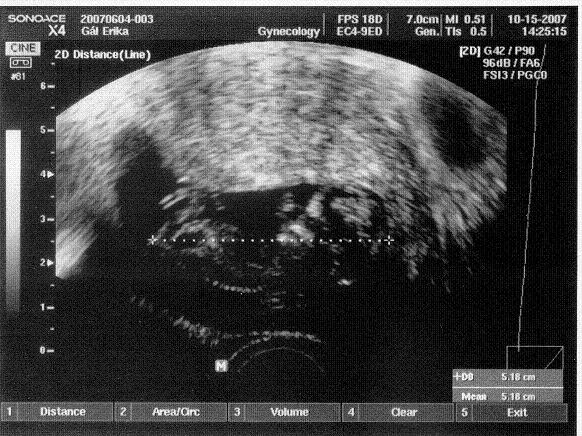

nagyon drukkolok neked! jó hírrel gyere az UH-ról!

javítsd a statisztikát!

Jövő hét szerdáig már nem kell olyan nagyon sokat aludni... gondolj arra, meddig eljutottál már!